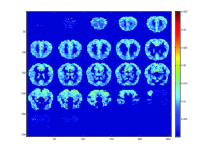

In Figure 4, we display 4 such groups of brain regions that are activated given a stimulus of a group of similar words; these words can be seen in Table 2, along with groups of similar questions that were highly correlated with the words of each group. Moreover, we were able to successfully identify high activation of the premotor cortex in Group 3, which is associated with concepts such as holding or picking items up.

Refer to caption

(a) Group 1

(b) Group 2

(c) Group 3

(d) Group 4

Figure 4: The latent brain images for the 4 word/question groups as shown in Table 2. We can see that for each different group, the activation pattern of certain brain regions is different. For instance, Group 3 refers to small items that can be held in one hand,such as a tomato or a glass, and the activation pattern is very different from the one of Group 1, which mostly refers to insects, such as bee or beetle. Additionally, Group 3, for instance, shows high activation in the premotor cortex which is associated with the concepts of that group.